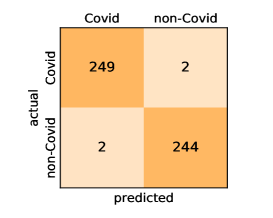

Here, we present and discuss the obtained results for detecting COVID-19 on the considered CT image datasets with different deep networks. We report the quantitative results along with the confusion matrices for every single architecture of the adopted networks.

On the SARS-CoV-2 CT dataset, ResNet101 achieves the best overall performance with respect to almost all evaluation metrics, with an average accuracy and F1-score of and , respectively. The model also achieves an average sensitivity rate of indicating that, on average, only two COVID-19 images are falsely predicted as negatives. It is also powerful enough to correctly identify all Non-COVID-19 cases with only one false positive resulting a specificity rate of . The highest sensitivity score of is achieved by the InceptionV3 model, where only one COVID-19 image is falsely predicted as negative on average. The SqueezeNet model obtains the lowest performance with respect to all evaluation metrics with a fairly acceptable average accuracy and sensitivity scores of and , respectively. Also the ShuffleNet architecture obtains satisfactory performance with approximately improvements on average for all metrics compared with SqueezeNet. Although the results obtained by these models are inferior compared with the rest of models, but they are more efficient. This matches their main objective of reducing the computational costs rather than improving their visual recognition abilities. The rest of models achieve competitive performance and very promising results with slight performance differences. Comparing the different variants of ResNet and DenseNet, we can see that the deeper variants from each architecture yield a slightly better performance. The deeper ResNet101 and ResNeXt101 show a marginal gain in performance compared with their shallower counterparts. The details about class-wise results for each model are summarized in the confusion matrices in Figure 9.

Our models achieve fairly good performance compared with the recently published work using the exact network architectures. This can bet attributed to a better optimization of our models and the effectiveness of our fine-tuning strategy using custom-sized inputs determined specifically for each architecture. Here, we see that DenseNet201 outperforms all other architectures. The model achieves average accuracy and sensitivity scores of and , respectively. It also identifies all COVID-19 images with only four images, on the average, are falsely predicted as Non-COVID-19. DenseNet169 achieves the second best average accuracy of and a very high sensitivity identical to the best model. The DenseNet121 and Xception models have nearly identical results for all evaluation metrics. We observe that small-sized networks such as ResNet18 achieves comparable results with other deeper models. The SqueezeNet and ShuffleNet models perform at a similar level of accuracy. The variants of the ResNeXt models have comparable results and perform as good as the different ResNet variants. A detailed analysis on the class-wise results for individual models is presented in the confusion matrices in Figure 10.